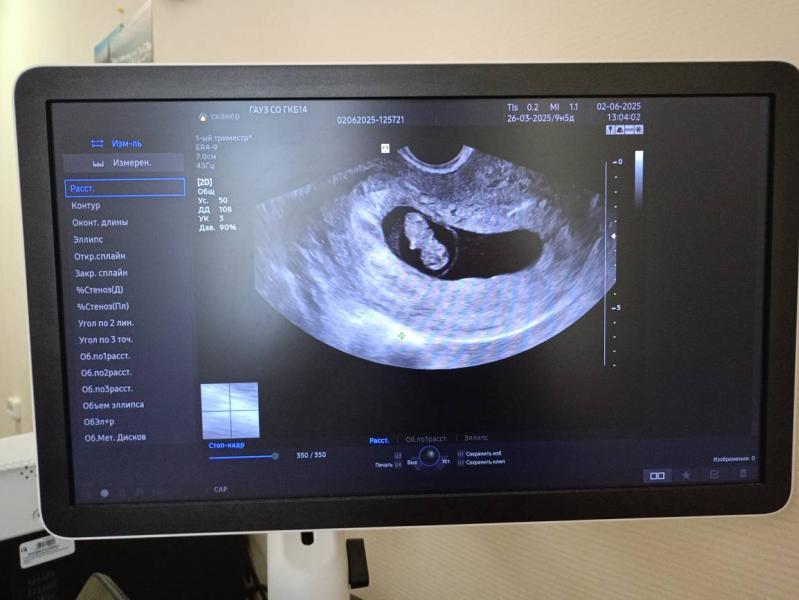

В понедельник 2ого июня я была на УЗИ и на приеме.

Начну пожалуй с УЗИ ( это было мое второе УЗИ, первое было на сроке 4-5 недель , тогда я только узнала о тебе и на следующий же день поехала на первое УЗИ 😅

По узи всё хорошо, срок беременности 9.1 день по малышу🤰Ручки и ножки только образовываются, скоро он будет полноценным человечком😍( Расти малыш!). Малыш прекреплен по задней стенке , я уверена, что он мальчик , сынок!

На фото второе и первое узи❤🔥